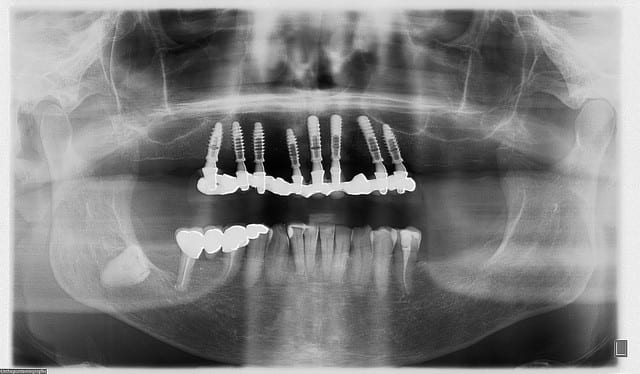

tous les implants sont en diamètre 3.7

certains (j'en fais partie) aiment bien plus large au niveau des secteurs molaire....mais vu que l'on a posé dans les septums, une augmentation de diamètre conduisait obligatoirement à une diminution de la surface de contact os/implant...d'où ce choix...

Blason dql7mj - Eugenol

je ne vais pas discuter le nombre d'implants qui n'est pas forcément un problème lorsqu'ils sont précisément posés et de diamètres corrects pour éviter une trop grande proximité entre-eux ce qui est le cas ici.

As-tu, Pluton, une pano pré-op à nous montrer qu'on se rende mieux compte de la situation initiale et as-tu objectivé la précision d'adaptation par friction en prenant quelques clichés rétroalvéoaires de contrôle ?

voilà Olivier...;-)

désolé pour la réponse tardive, j'ai un boulot monstre en ce moment...

pano initiale et planche 3D montrant qu'en fait les molaires ne tenaient quasi plus que par les racines palatines...

pour la très grande précision d'emblée, Posit a répondu, nous sommes quelques praticiens à poser ainsi...

seules vraies difficultés: avoir parfaitement compris le système du guide Positdental et connaître/maîtriser parfaitement son système implantaire...